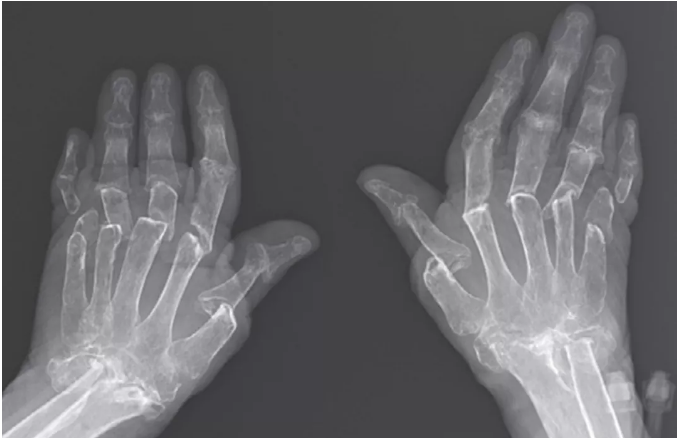

查体发现双手尺骨偏斜,双手掌指关节、手腕、肘部、膝关节和左脚踝关节有压痛和肿胀。手部的专科查体还显示手指变短,手指失去主动屈曲,无法握拳。在远端指骨施加牵引,可以使手指伸展,当指骨松开时,手指回到原来的位置。

手部平片显示远端尺骨、桡骨、腕骨、掌骨和指骨出现严重的骨质溶解(见上图)。观察到的伸缩现象是这种骨吸收的结果。最后患者接受了托法替尼、甲氨蝶呤、小剂量泼尼松和伊班膦酸的治疗,这些治疗虽然减轻了疼痛和肿胀,但无法改变手的功能。